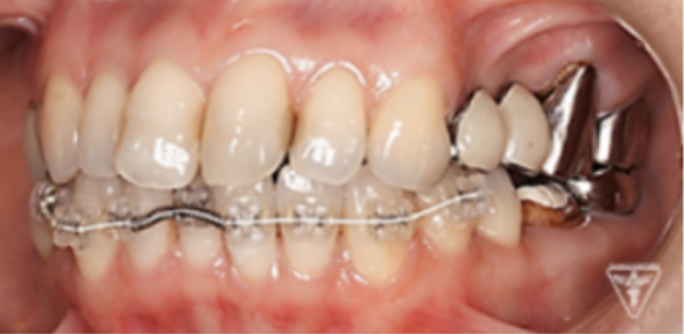

矯正治療

矯正治療による歯軸、叢生改善

インプラント